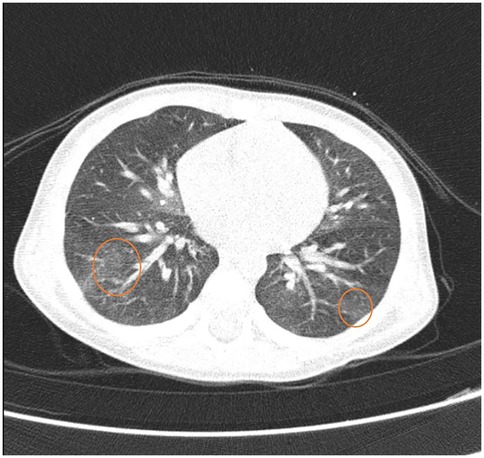

Heiner syndrome, although rare in pediatric practice, can cause cough, wheezing and only in rare cases hemoptysis. Heiner syndrome should be considered in any child presenting these respiratory symptoms and radiological evidence of alveolar infiltrates, especially when accompanied by signs of food allergy-most notably cow's milk protein allergy, although other foods seem to be involved. The use of probiotics should be evaluated with caution in these children. We report a case of a 1-year-and-6-month-old female patient who presented at the Pneumology Clinic with a one-day history of blood-tinged sputum. Although the patient had a known history of cow's milk protein allergy and well-controlled asthma, the occurrence of hemoptysis, even though in small quantities, raised concerns to the family. A second episode of hemoptysis appears when she received egg and probiotic. After correlating the patient's medical history with clinical, laboratory, and imaging findings, a diagnosis of Heiner syndrome was established. The patient received emergency treatment followed by bronchodilators, corticosteroid therapy, and restricted diet for cow's milk protein and egg. The patient's condition improved immediately after treatment and remained stable at the 5-month follow-up. The differential diagnosis with idiopathic pulmonary hemosiderosis must not be overlooked, due to its more severe clinical course and higher risk of complications.